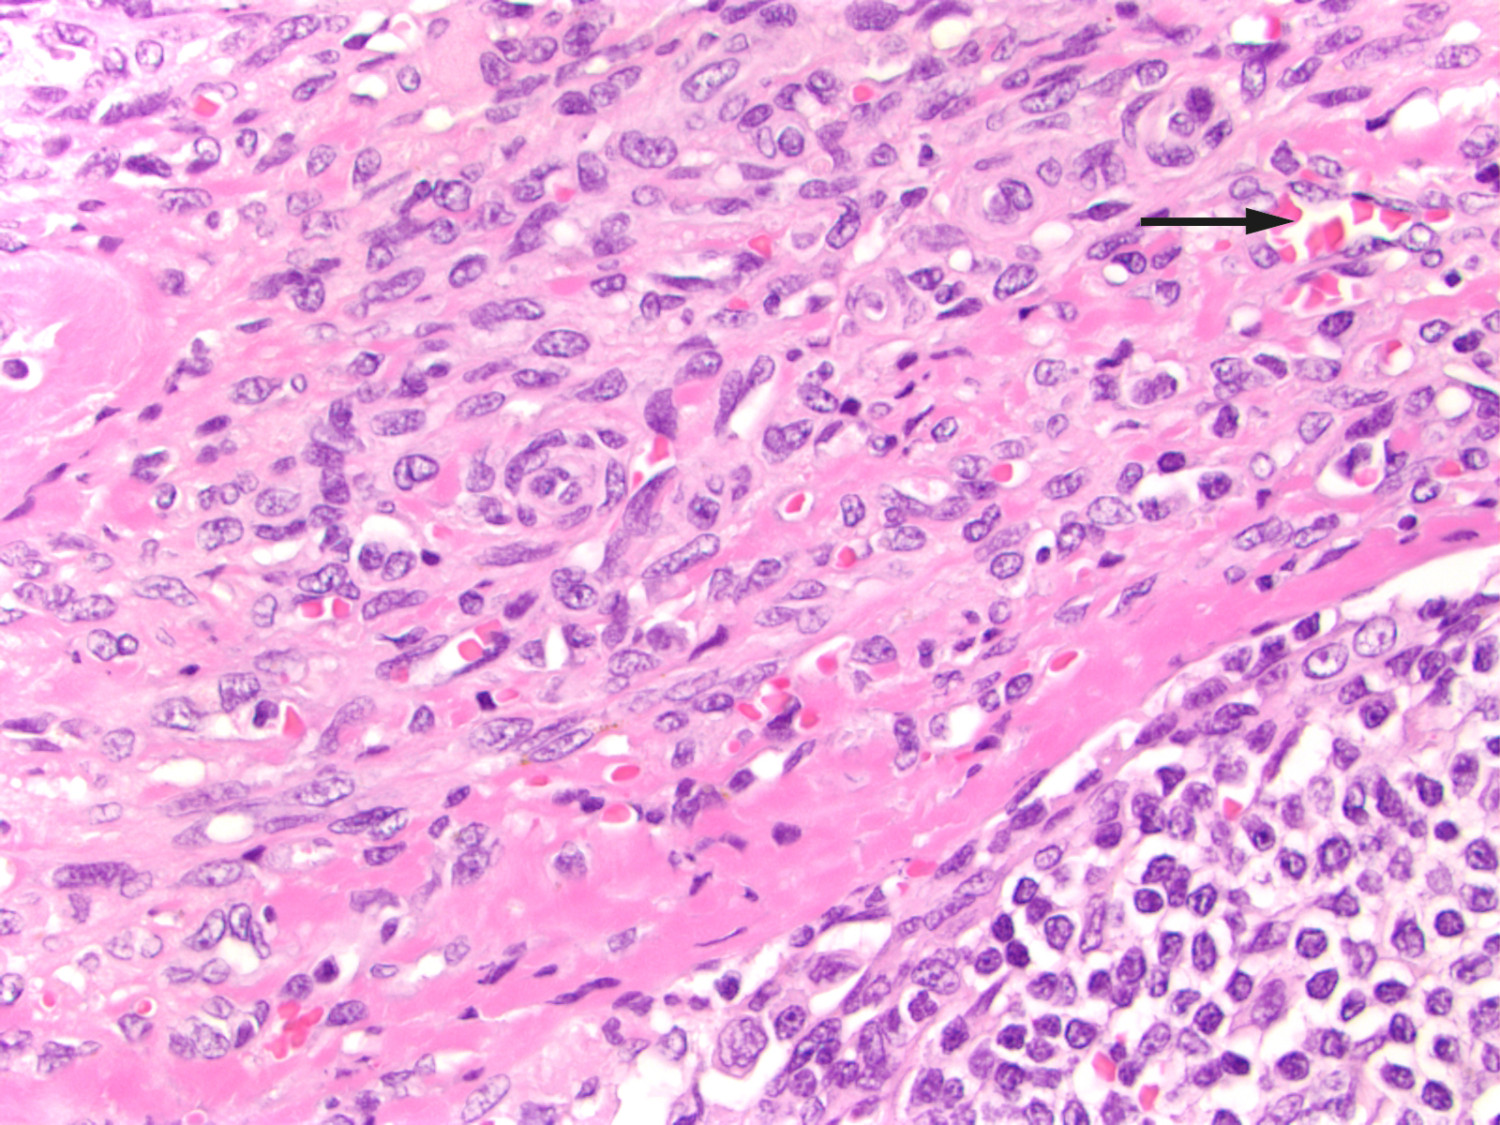

Etter denne episoden ble han ikke ordentlig bra. Han ble nok en gang innlagt og gastroskopert, og i ventrikkelen så man tre rødlige, puteformede forandringer med hemangiomaktig utseende. Forandringene ble biopsert. Ved sammenligning av makroskopisk gastroskopifunn med endoskopiatlas så man at funnet var patognomisk for gastrointestinalmanifestasjon av Kaposis sarkom (2). Patologen ble bedt om å undersøke ventrikkelbiopsier med tanke på dette. Pasienten viste også frem blålilla hudforandringer både på høyre underarm og venstre vrist som hadde økt i størrelse de siste fem månedene (figur 1). Hudforandringer på armen ble biopsert, og histologisk undersøkelse bekreftet Kaposis sarkom både i ventrikkel- (figur 2) og hudbiopsi. Begge biopsiene viste HHV-8-positivitet (humant herpesvirus 8). Lymfeknutebiopsien fra fem år tidligere ble revurdert til også å være forenelig med Kaposis sarkom (figur 3). Etter at diagnosen var stilt, ble det startet behandling med liposomalt doksorubicin intravenøst. På tross av behandlingen utviklet sykdommen seg videre med spredning til leveren, og pasienten døde litt over to år etter at diagnosen var stilt.

Kaposis sarkom er en multifokal, lavgradig, vaskulær tumor som involverer hud, mukosa og viscera (3). Sykdommen ble først beskrevet i fem kasuistikker av den østerrikske legen Moritz Kaposi i 1872, og han kalte tilstanden «idiopathic multiple pigmented sarcoma» (4, 5). I kasuistikkene beskrev han ødem og blålilla noduler på huden, mest på hendene og føttene. Ved mikroskopisk undersøkelse av hudbiopsier beskrev han små runde celler (spolceller), små hemorragiske områder med noduler og pigment (hemosiderin). Alle pasientene døde i løpet av to–tre år.

Histopatologiske funn er identiske ved de fire formene, og det typiske histologiske funnet er spolceller. Sykdommen progredierer i tre histologiske stadier: Det første kalles «patch stage» og er preget av flate, makuløse forandringer. Neste stadium kjennetegnes av plakk, mens det siste, tumorstadiet, preges av nodulære lesjoner. De histologiske forandringene kan lett oversees (5).